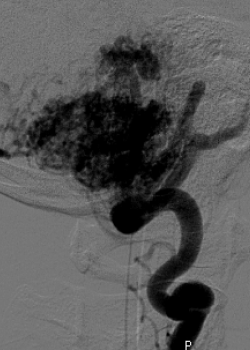

Katherine collapses in our kitchen while James naps in the other room. She is rushed to UCLA Medical Center, where Dr. Nestor Gonzalez chooses to operate on the largest AVM he has ever seen. Her survival will take a miracle.

Over half of Katherine’s cerebellum is removed and many vital intra-cranial nerves are sacrificed, risking a vegetative state. After 16 hours of micro-brain surgery, Katherine lives.